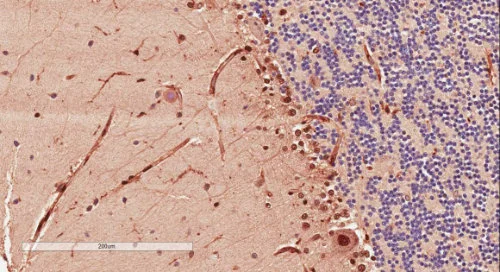

| EB11147 | Goat Anti-SYNGAP1 (aa1169-1183) Antibody | Pep-ELISA, WB, IHC, IF | Human, Mouse, Rat, Dog, Pig, Cow | 100µg/200µl |